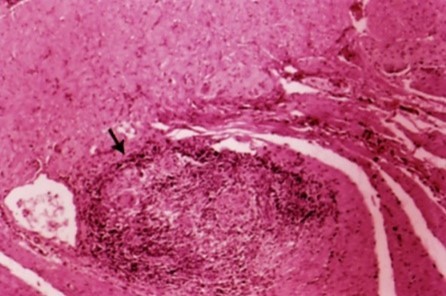

Vilken sjukdom och vad ses?

Crohns sjukdom med ett granulom

- Transmural inflammation

- Sårbildning

- Granulom

- Kryptabcesser

När kan detta ses vid mikroskopisk bild?

Crohns